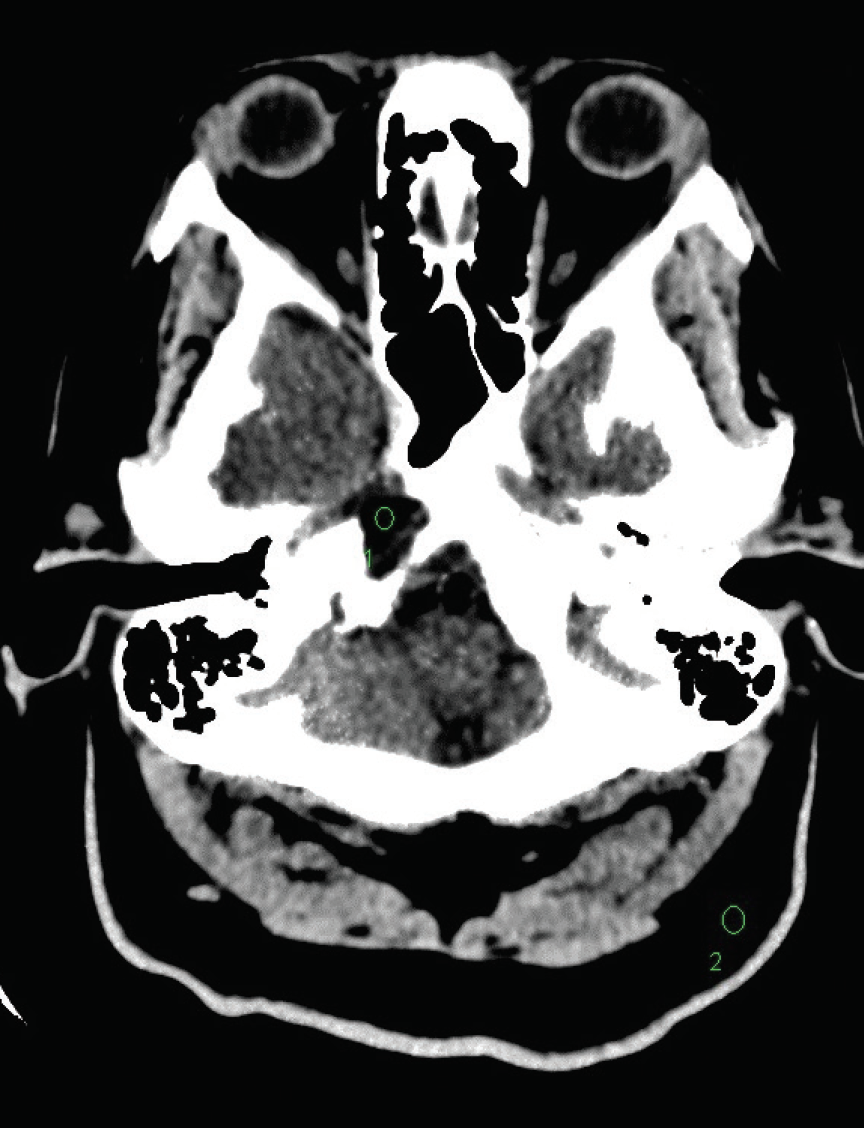

A 56-year-old woman presented with subjective right-sided numbness and paresthesias in the upper and lower extremities, along with fatigue and dizziness.